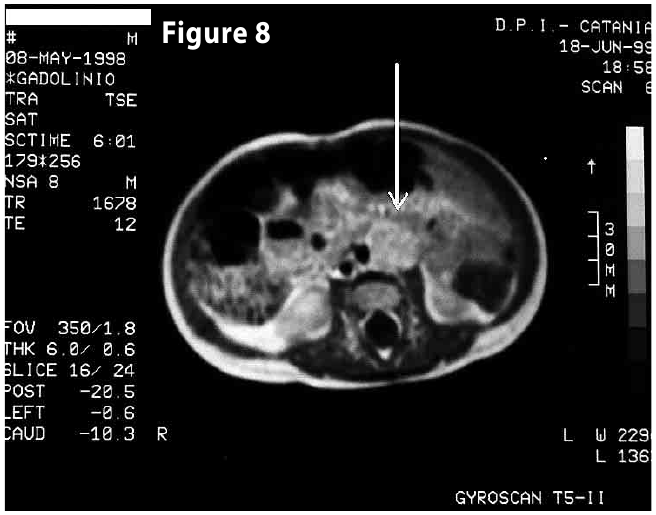

Complete objective response of neuroblastoma to biological treatment.

Figure8